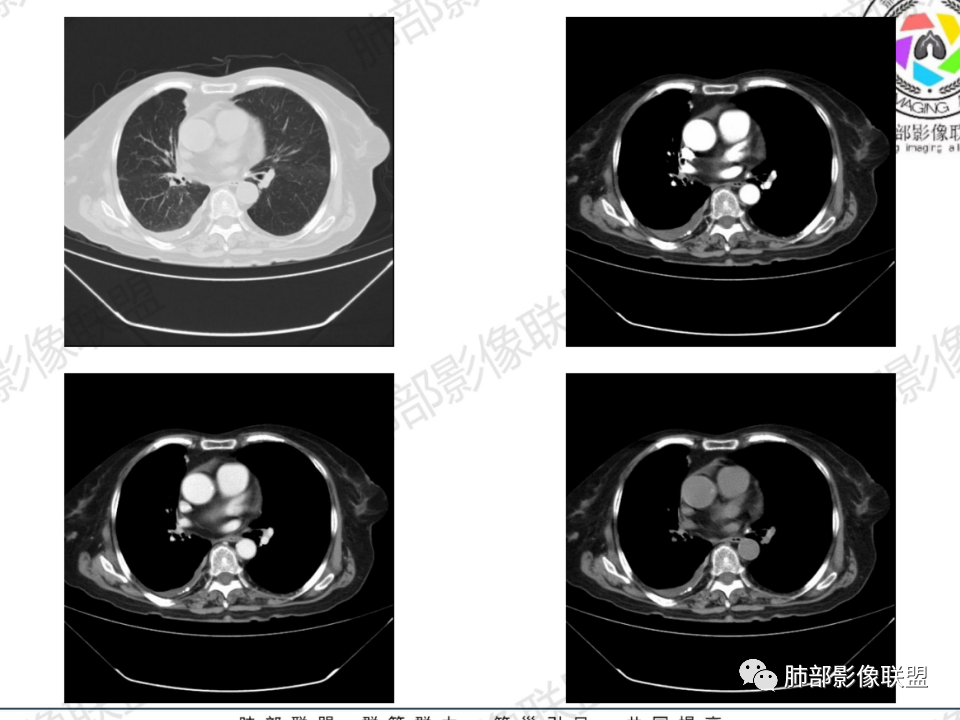

结核是肯定有。现在最大问题是尖段

近端显示不清,但是远端是粘液栓,可以认为是还行的

如果是近端鳞癌,远端应该会堵塞,不会整个肿块里面还有较为通畅的支气管

这个区域我们看到密度与周围一致,并不是肺癌伴周围不张的感觉,所以鳞癌暂时是不支持的

临床信息:老年女性,亚急性病程,咳嗽发热。有激素使用史。既往有淋巴结结核病史。肿瘤标记物Ca125升高。血沉升高,C反应蛋白轻度异常。 影像所见:右侧胸廓相对狭小,右肺上叶不规则团块影贴附纵隔旁,轻度分叶,整体密度较均匀,偶见钙点。

相应上叶尖端及前段支气管开口未能追踪(阻塞),开口处见钙化。病灶渐进性强化,并衬托出较完整尖段及前段含液支气管影。支气管开口区域未见异常高密度强化(如类癌等)及相对乏血供区(如鳞癌)。病灶区未见液化坏死。右上纵隔及胸廓入口区未见病灶胸膜外突破(栽赃)。